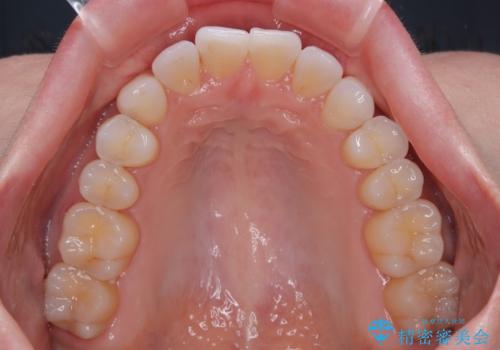

前歯のデコボコをインビザラインで綺麗に

- 上下前歯の叢生を気にして来院された患者様です。

インビザラインでの治療を希望されていて、デコボコの程度が中等度であり、安価なパッケージにて対応可能と判断されたため、インビザライン・モデレートを用いて矯正治療を行うこととしました。